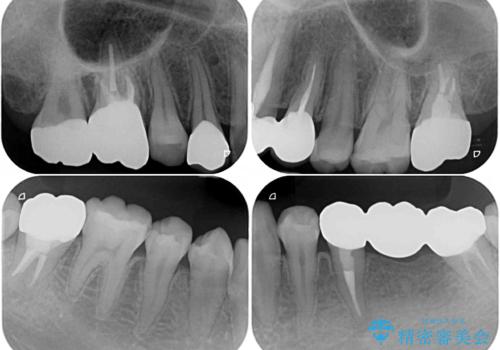

むし歯だらけの奥歯 セラミッククラウンによるむし歯治療

- 奥歯のむし歯を気にして来院された患者様です。

痛みのある歯が多く、根管治療が必要と診断されました。

左下の歯は、クラウンを装着するために必要な高さが足りないため、歯冠長を延長するための外科処置を行うこととしました。

根管治療や歯周外科処置後にフルジルコニアクラウンにて補綴治療することとしました。